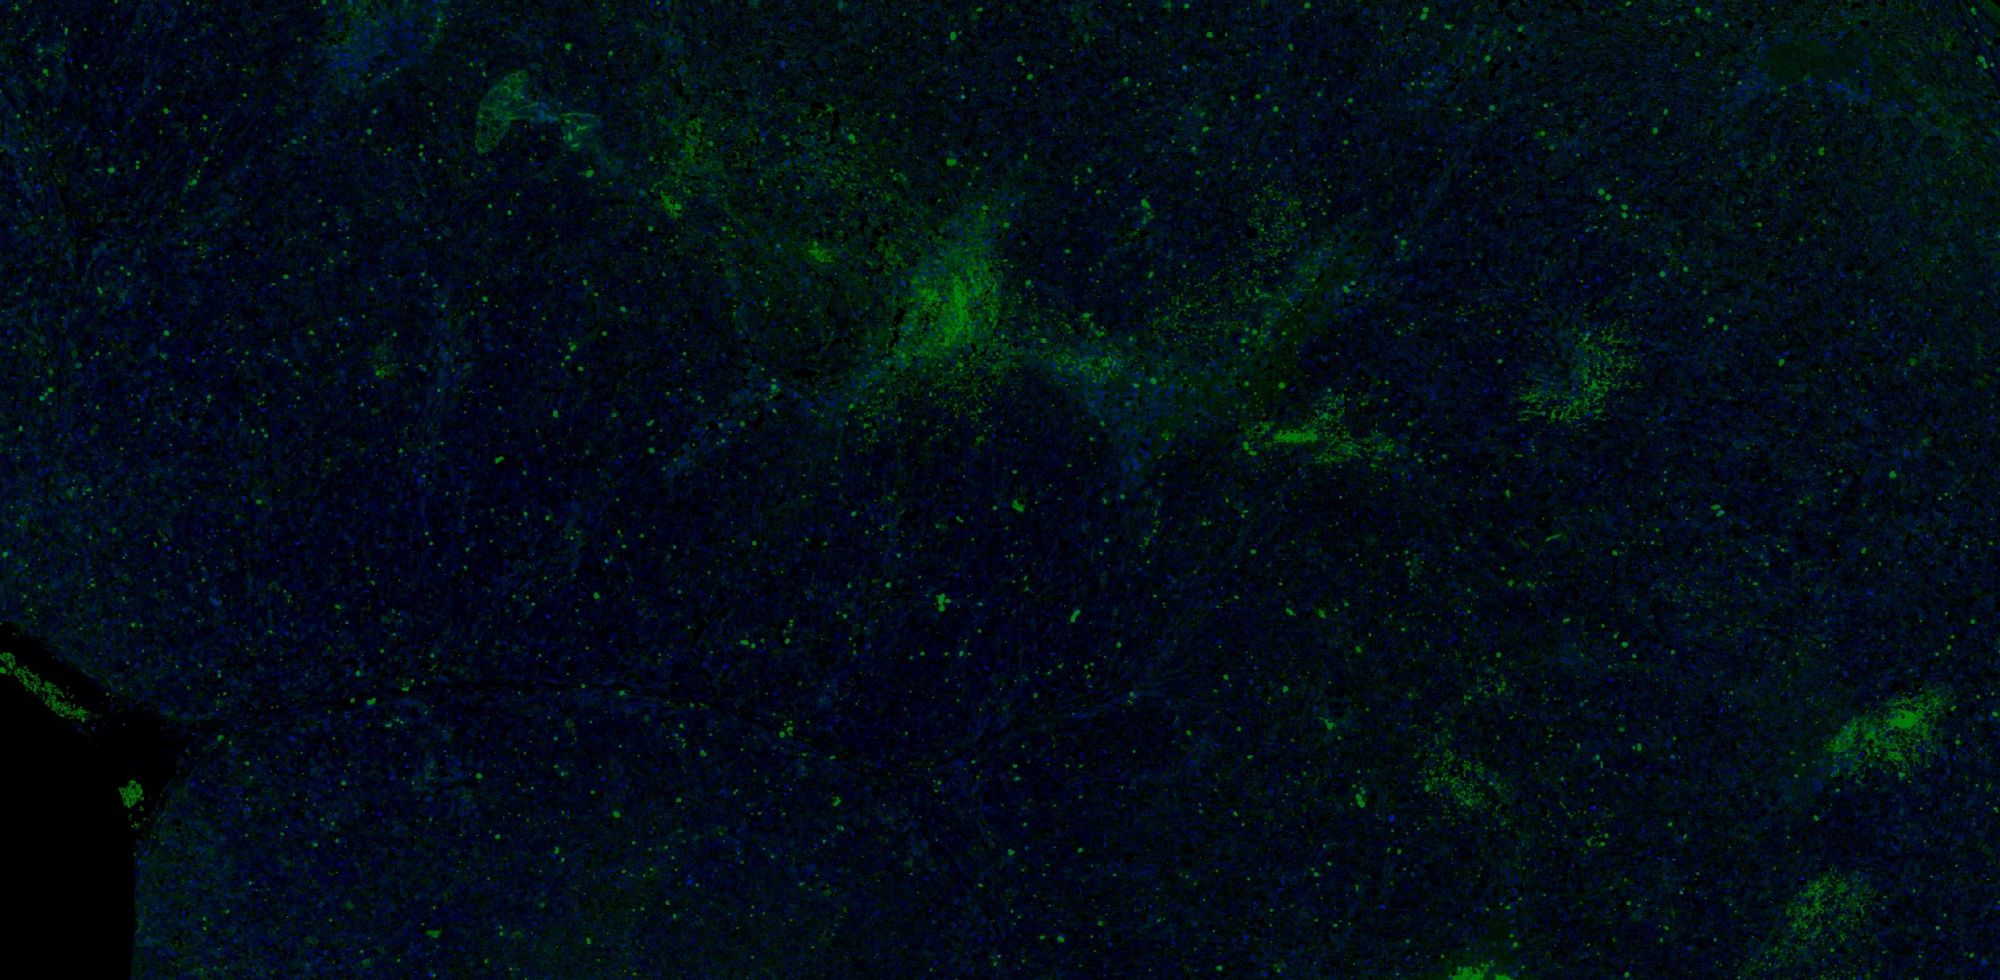

免疫學的基本反應是抗原-抗體反應。由于抗原抗體反應具有高度的特異性,所以當抗原抗體發(fā)生反應時,只要知道其中的一個因素,就可以查出另一個因素。免疫熒光技術(shù)就是將不影響抗原抗體活性的熒光色素標記在抗體(或抗原)上,與其相應的抗原(或抗體)結(jié)合后,在熒光顯微鏡下呈現(xiàn)一種特異性熒光反應。

案例展示